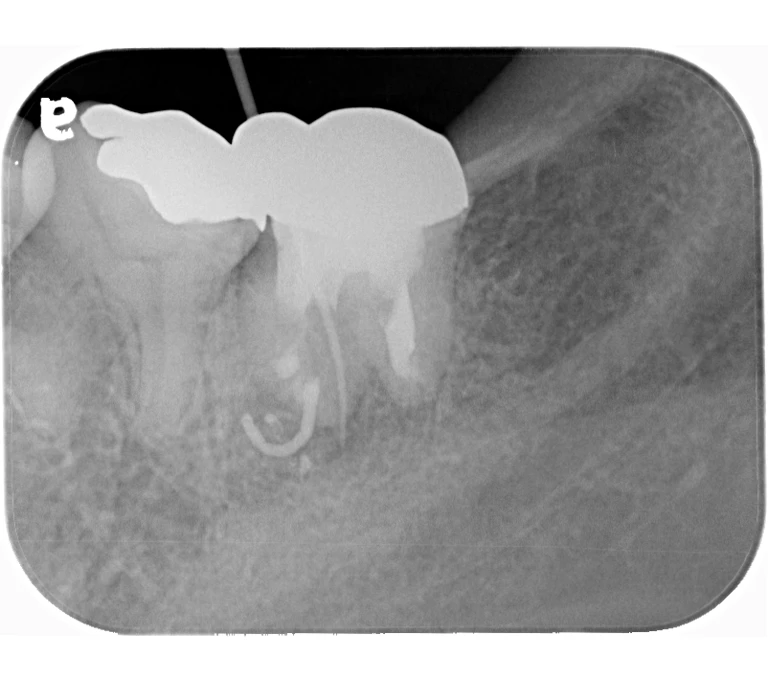

case 1.

治療前

治療後

| 主訴 | 右下歯ぐきの腫れ。 他院で抜歯と言われ、セカンドオピニオン希望でご来院。 |

|---|---|

| 治療期間 | 1か月 |

| 治療費 | 約2万円 |

| 治療内容 | ラバーダム、マイクロスコープ下にて根管治療を施術。歯肉腫脹と疼痛は消失し補綴物を作製し治療終了。治療後のレントゲン写真は2年後のものです。 |

| 治療のリスク | マイクロスコープやCTを使用し、可能な限り精密な根管治療を行っていますが、歯根の形態や病変の大きさ、過去の治療履歴などにより、治癒が得られない場合があります。 また、治療後に再感染や歯根破折が生じることもあり、その場合は再治療や抜歯が必要となることがあります。 治療結果には個人差があり、すべての症例で同様の経過を保証するものではありません。 |